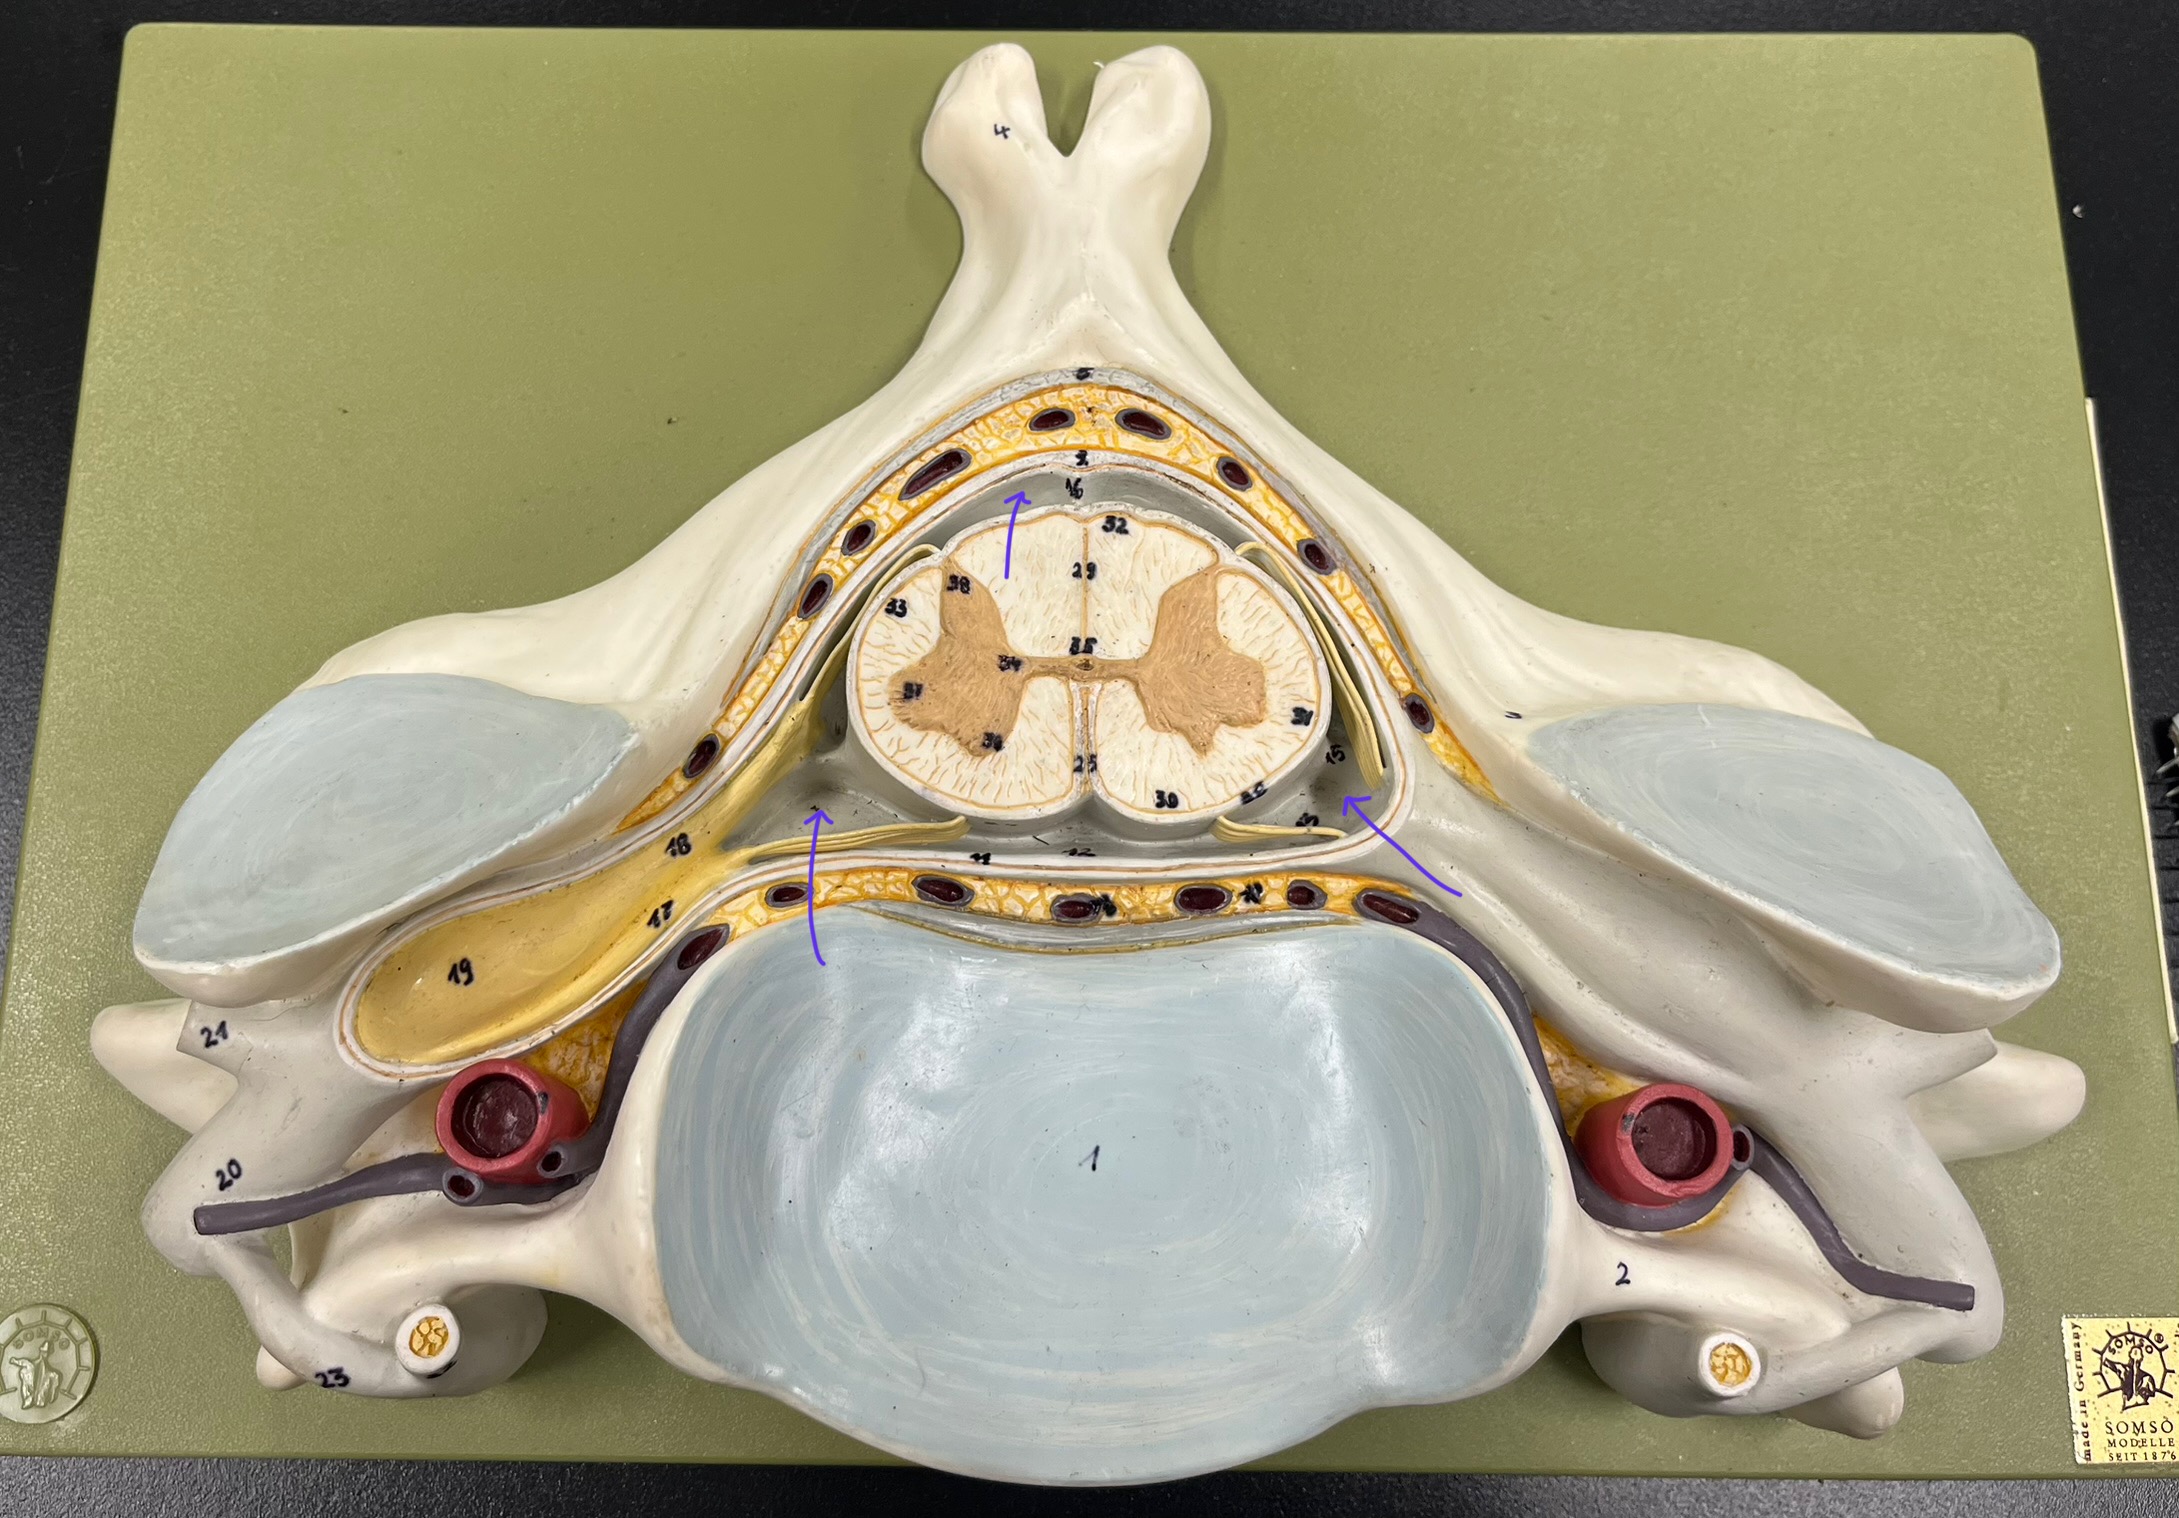

epidural space

dura mater

subdural space

arachnoid mater

subarachnoid space

pia mater

denticulate ligaments

What is the groove here?

anterior median fissure

posterior median sulcus

posterior (dorsal) horn

anterior (ventral) horn

lateral horn (selected models)

gray commissure

central canal

anterior column

lateral column

posterior column

white commissure

posterior (dorsal) root ganglion

What is the bulb here?

posterior (dorsal) root ganglion

posterior (dorsal) root

posterior (dorsal) root

anterior (ventral) root

anterior (ventral) root

dorsal ramus

dorsal ramus

ventral ramus

ventral ramus

rami communicantes

rami communicantes

sympathetic chain ganglia

sympathetic chain ganglia